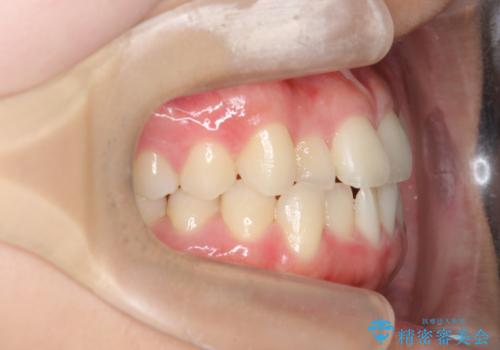

ガタつきの改善 マウスピース矯正治療

- 歯のがたつきの改善を求めて、矯正治療を希望され来院されました。

少量の歯のディスキング、歯列弓拡大、アタッチメントを装着することで審美的な歯列へとマウスピース矯正インビザラインを用いて治療を行います。

マウスピース矯正は装着時間の遵守が非常に大切ですが、しっかりと20時間/日以上の装着を守っていただいたおかげで良好な治療結果を得ることができました。